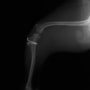

■ 症例20 ポメラニアン 8ヶ月 1.8kg

左右膝蓋骨脱臼 グレードⅢ

2ヶ月前から間欠的跛行が認められ、両膝の膝蓋骨脱臼整復術を行った。

手技は縫工筋及び内側広筋の解放、脛骨粗面の外側転位、滑車ブロック形造溝術、内外側関節包の縫縮を選択し実施した。

右側の膝蓋骨脱臼は上記手技で整復されたものの、左側はそれのみでは膝蓋骨が浮く様子が認められた。その為、PDS縫合糸にて膝蓋靱帯を1糸のみ縫合し、靱帯の縫縮を行った。

膝蓋骨脱臼は膝関節における膝蓋骨の内外側の脱臼と定義されるが、時として単純な内外の脱臼ではなく、膝蓋骨が大きく前方に浮き上がるように脱臼する場合がある。特にトイプードルやポメラニアンといった犬種に多く認められる。

内側脱臼に加えて前方への浮き上がりを矯正する為に、従来より脛骨粗面転移により膝蓋靭帯を外方と下方に引っ張り、固定する方法を選択する。膝蓋骨の前方への浮き上がりが軽度の場合は、従来法ではなく関節包の縫縮で対応していた。しかし、一部の症例で膝蓋骨の動きが悪くなり伸展機構が円滑に機能せずロボット様歩行になるケースがあった。

その為、膝蓋靭帯自体を縫縮する方法を採用した。この方法により、膝関節の伸展機構を妨げず膝蓋骨の軽度の浮きを矯正することが可能となった。

本症例の経過は良好である